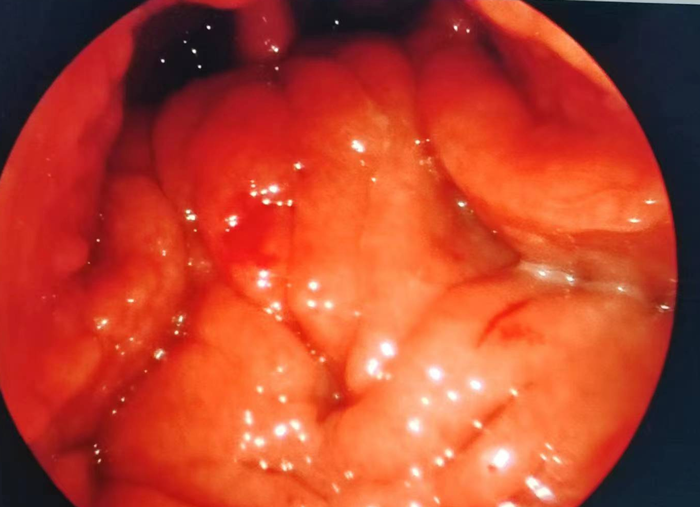

耳鼻咽喉科主任胡少爭(zhēng)

對(duì)慶慶仔細(xì)進(jìn)行

耳鏡和鼻鏡等相關(guān)檢查

除了已經(jīng)形成典型的

腺樣體面容以外

腺樣體肥大

已占據(jù)鼻咽部空間約80%

同時(shí)發(fā)現(xiàn)鼓室內(nèi)有積液

腺樣體通俗講

就是長(zhǎng)在鼻咽部的

“小肉球”

外形似半個(gè)剝皮桔子

表面不平

大概3、4瓣砂糖橘大小

當(dāng)它受到感染等

刺激“變胖”時(shí)

就是腺樣體肥大